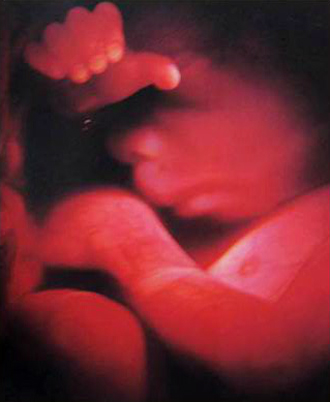

- 필수 검사

- 산전진찰 및 복부 초음파 (1회/4주)

- 임신성 당뇨 검사

- 빈혈, VitD검사

- 4차원 후기 정밀 초음파 (26~28주)